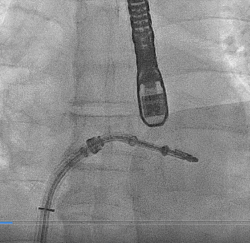

▲ MitraClip释放